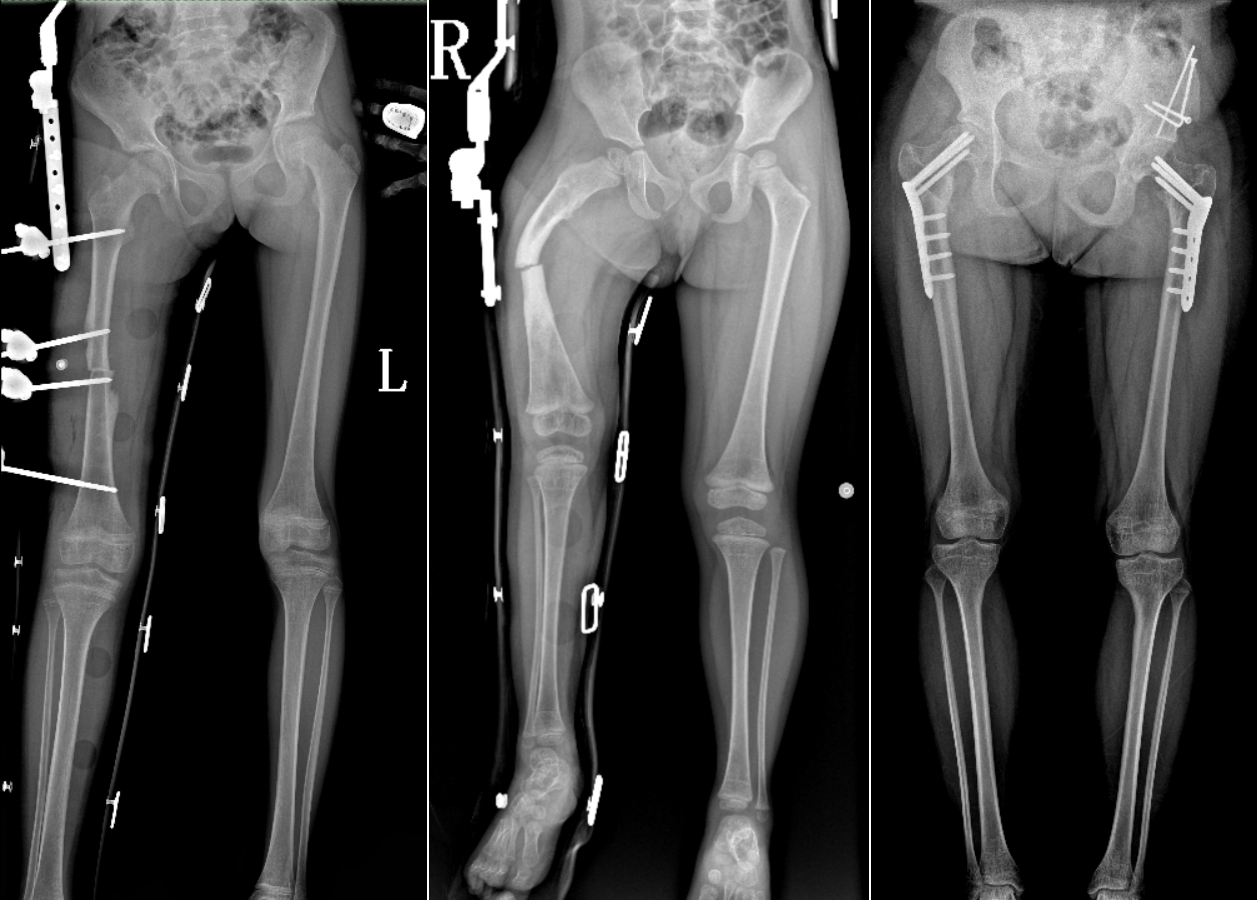

DR是臨床骨科的重要檢查手段之一。在骨科檢查中,脊柱矯形、長骨骨折、腰椎退行性病變等,需要采集脊柱、下肢全景圖像,輔助醫(yī)生臨床診斷,從而制定科學(xué)的治療方案,普愛醫(yī)療的大視野平板動態(tài)DR就像是一座橋梁,連接起現(xiàn)代醫(yī)療技術(shù)與當(dāng)?shù)厝嗣竦尼t(yī)療需求。

普愛醫(yī)療自主研發(fā)的大視野平板動態(tài),采用17"*34"的有效視野,一次曝光即可得到全脊柱或全下肢影像。相較于多張攝影再軟件拼接的DR設(shè)備,PLX8600解決了拼接圖像存在密度不均勻,拼接處圖像配準(zhǔn)和放大效應(yīng)等問題,給臨床帶來了真正的大視野影像解決方案。

除了常規(guī)靜態(tài)攝影外,PLX8600的大平板具備動態(tài)透視和點(diǎn)片功能,能夠很好地觀察復(fù)雜部位病灶,有效地抓取關(guān)鍵幀,降低患者多次攝片的概率。如:全脊柱狀態(tài)評估、長骨關(guān)節(jié)活動度、下肢靜脈造影瓣膜功能評估、消化道功能評估、脊髓造影等更多大視野臨床應(yīng)用,“多面手”都能輕松應(yīng)對。